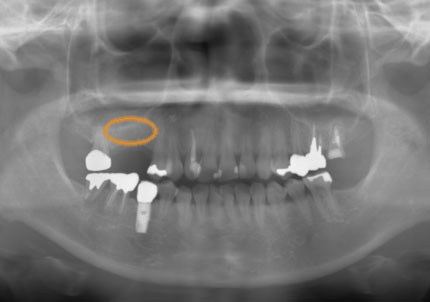

2.右側上顎洞サイナスリフト後にインプラント埋入

↑ サイナスリフト術前

↑ サイナスリフト術後

3.右上インプラント補綴物装着(2009年7月24日)

↑ 右上サイナスリフト後にインプラント埋入

4.左上下7番インプラント補綴物装着(2010年5月24日)

5.右上7番インプラント(2013年11月6日)

6.右下6,7番インプラント(2017年9月15日)

7.左上6番インプラント(2021年2月21日)

8.初診より現在に至る

強い歯ぎしり、くいしばりで奥歯の歯牙破折、深い虫歯で保存不可能となり全顎治療となる。